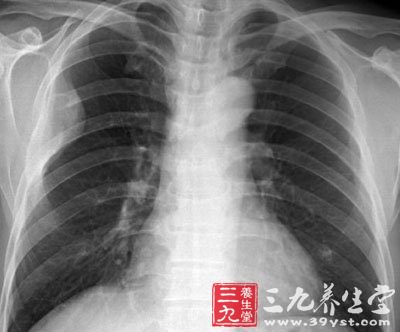

支原体肺炎-三九养生堂

400x332 - 23KB - JPEG